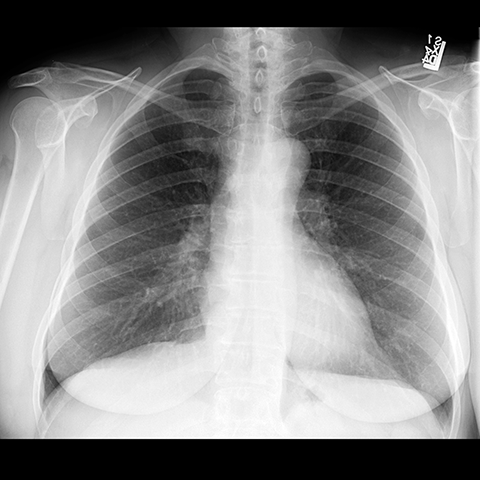

PA of Normal Trachea and Bronchi [1 of 5]